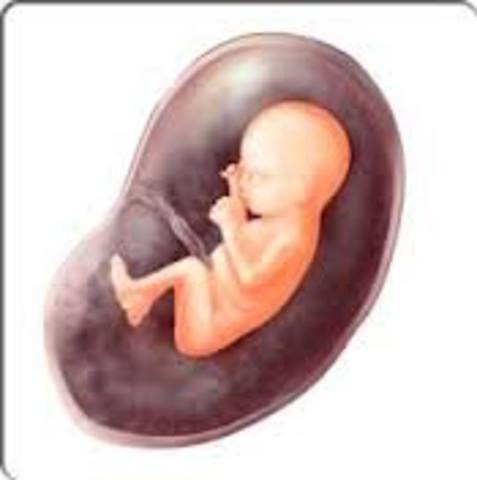

Week 12

By now, your baby weighs a full half-ounce and is about the size of a large plum. Most of his systems are in place, though there's still plenty of maturing to do. For one thing, his fetal digestive system is beginning to practice contraction movements necessary for eating, and his bone marrow is busy making white blood cells — weapons against germs once he's out of your safe haven.